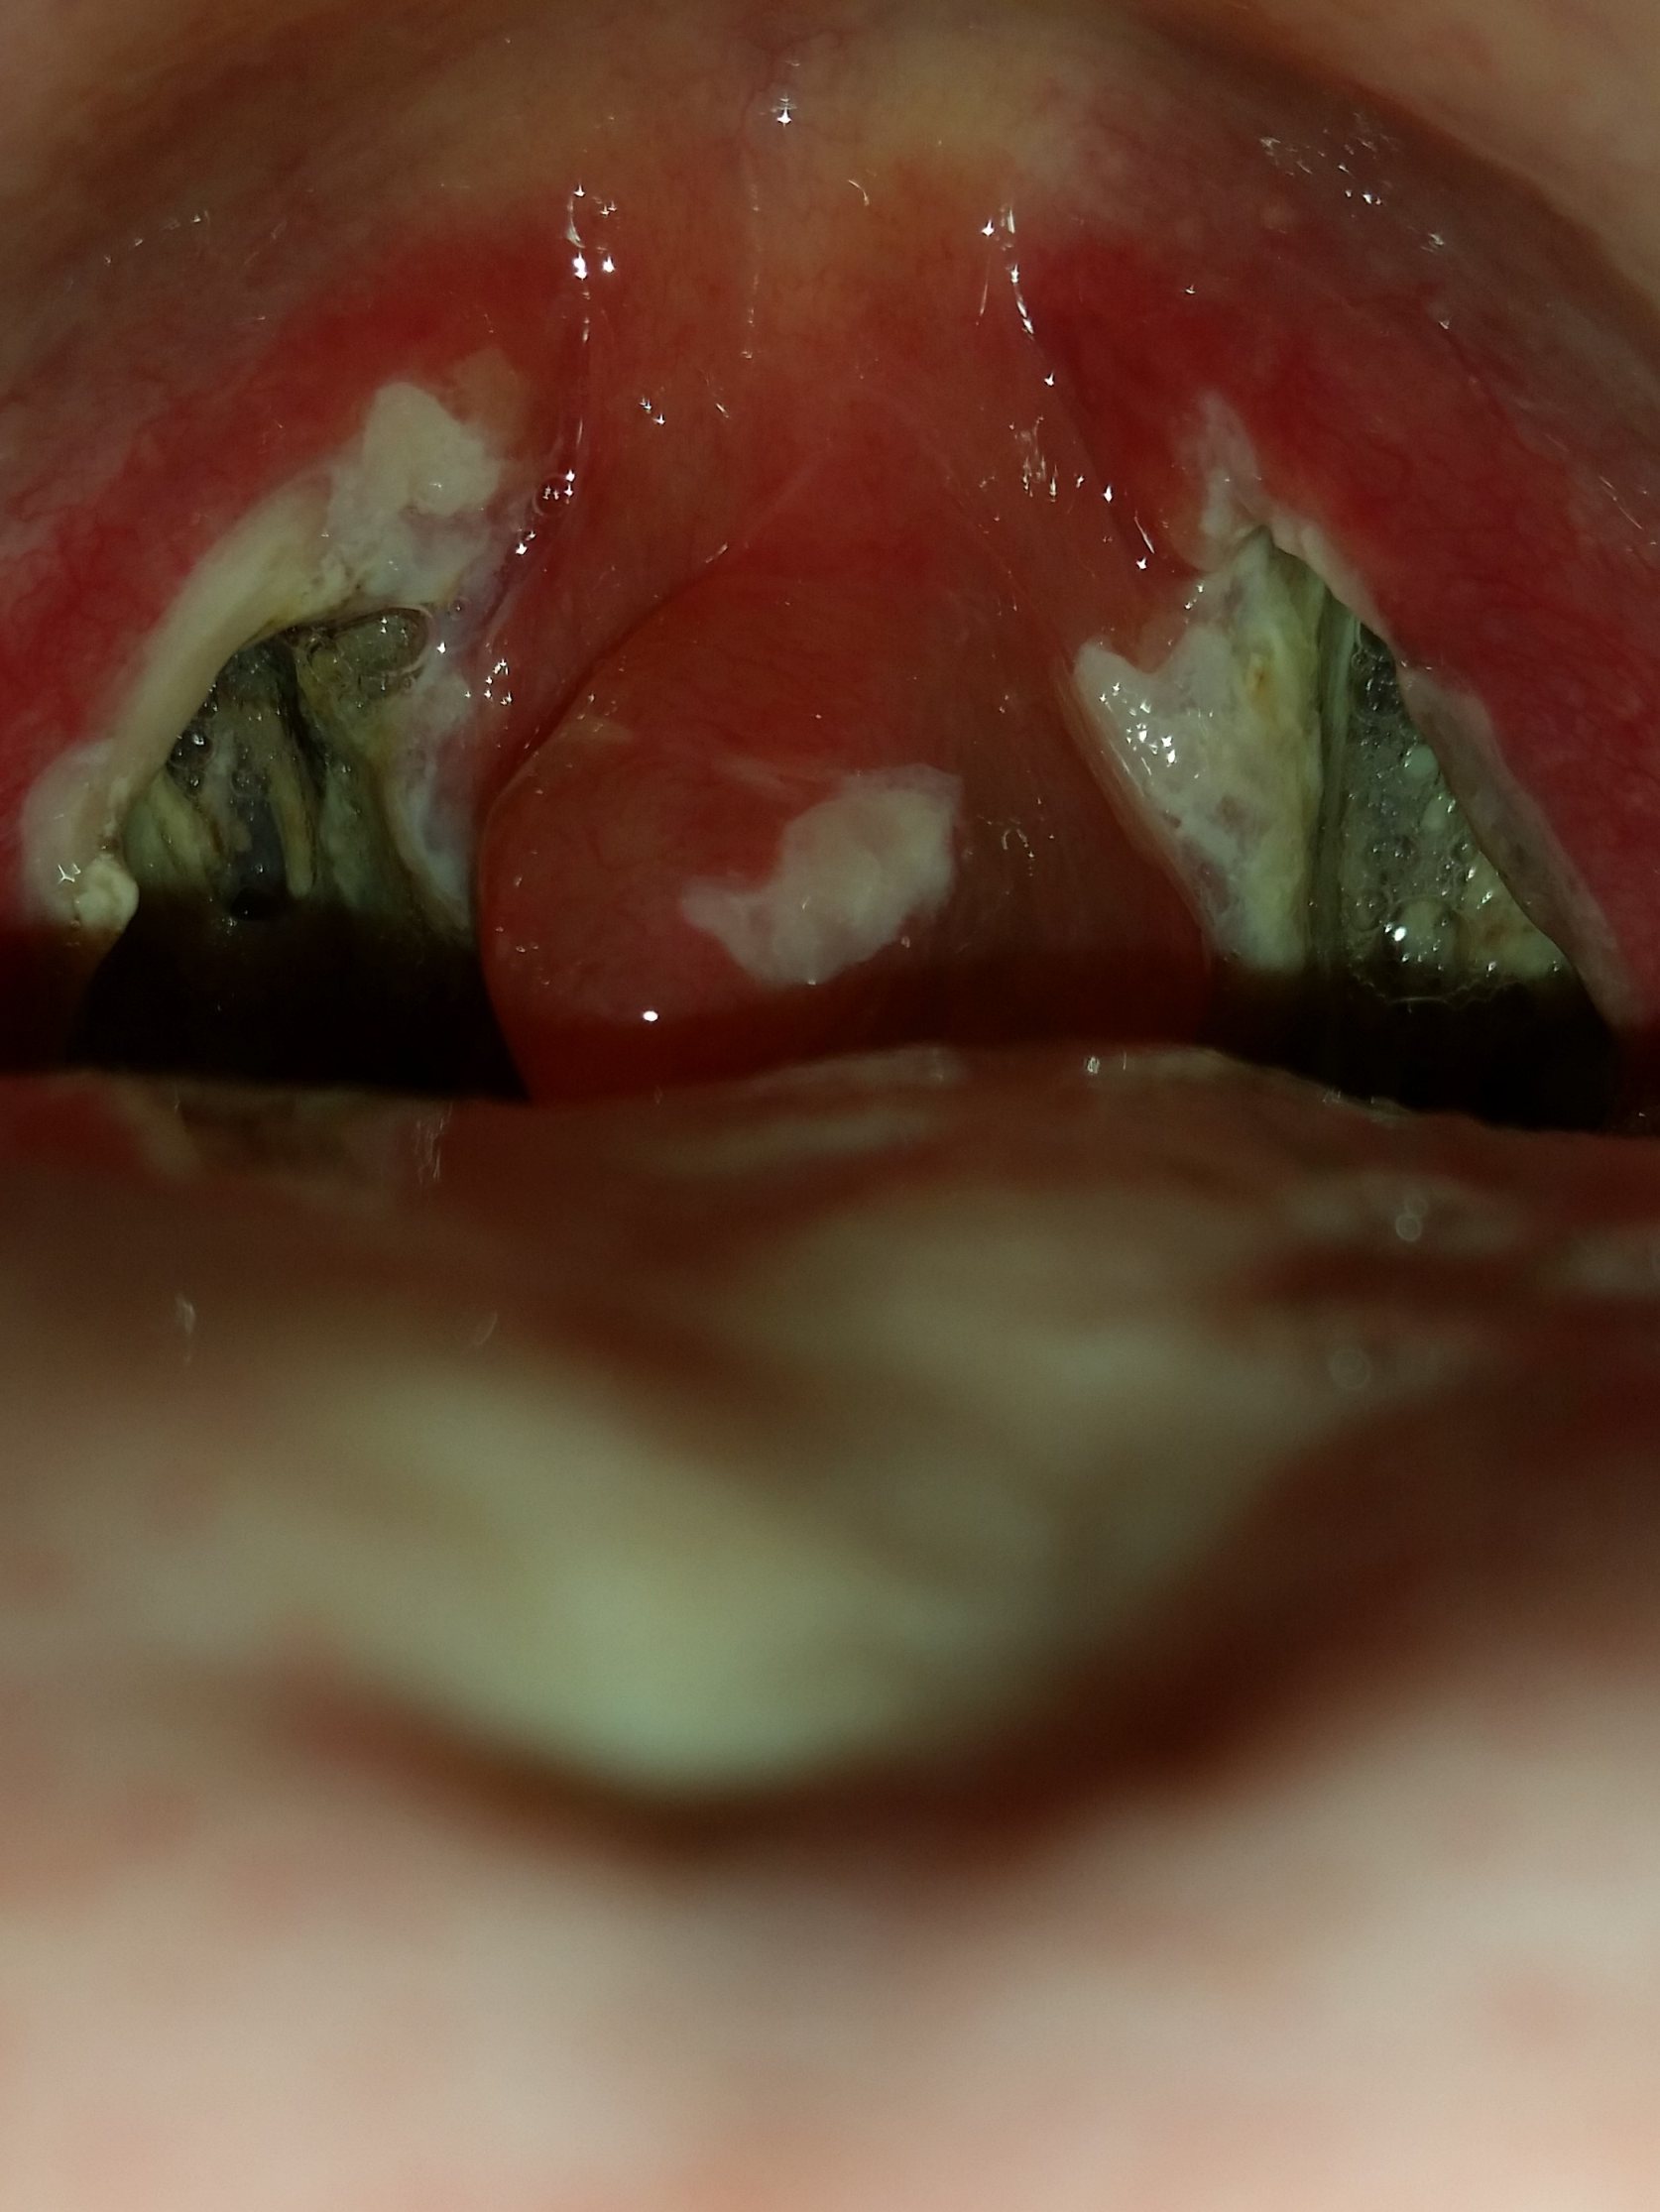

Mandel OP – Bilder Dokumentation Heilungsprozess

- Mandeloperation Tag 1

- Mandeloperation Tag 2

Nach der Operation bildeten sich direkt die weiß, grünlichen Beläge (Fibrinbeläge).

Bis sich die Beläge lösten hatte ich einen leicht „fauligen Mundgeruch“.

Ab dem Tag 9 lösten sich langsam die Beläge. (Ein ziemlich brennendes Gefühl)